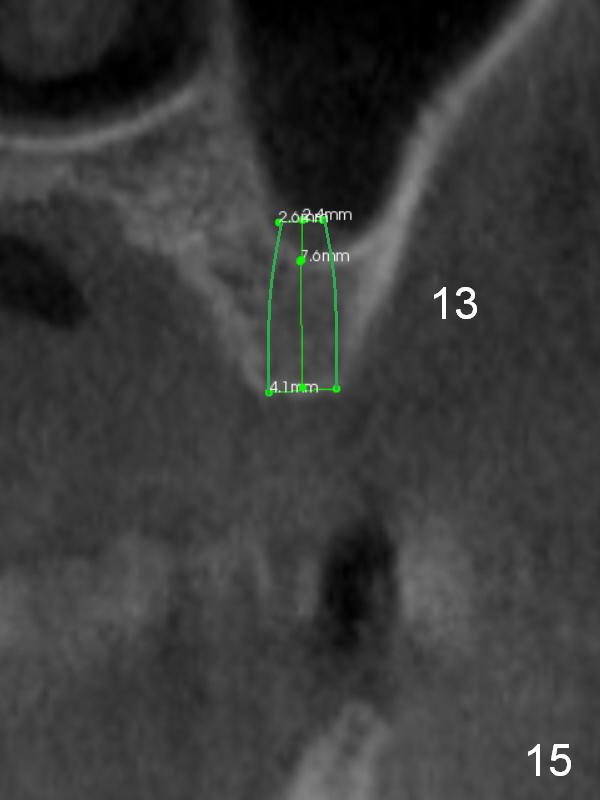

The ridge at #12 becomes a little bit wider and a 1-piece implant is placed palatal (Fig.13). The height of the alveolus and low bone density at #13 are limiting factors (Fig.14). The solutions will be sinus lift and bone condensation (Fig.15).